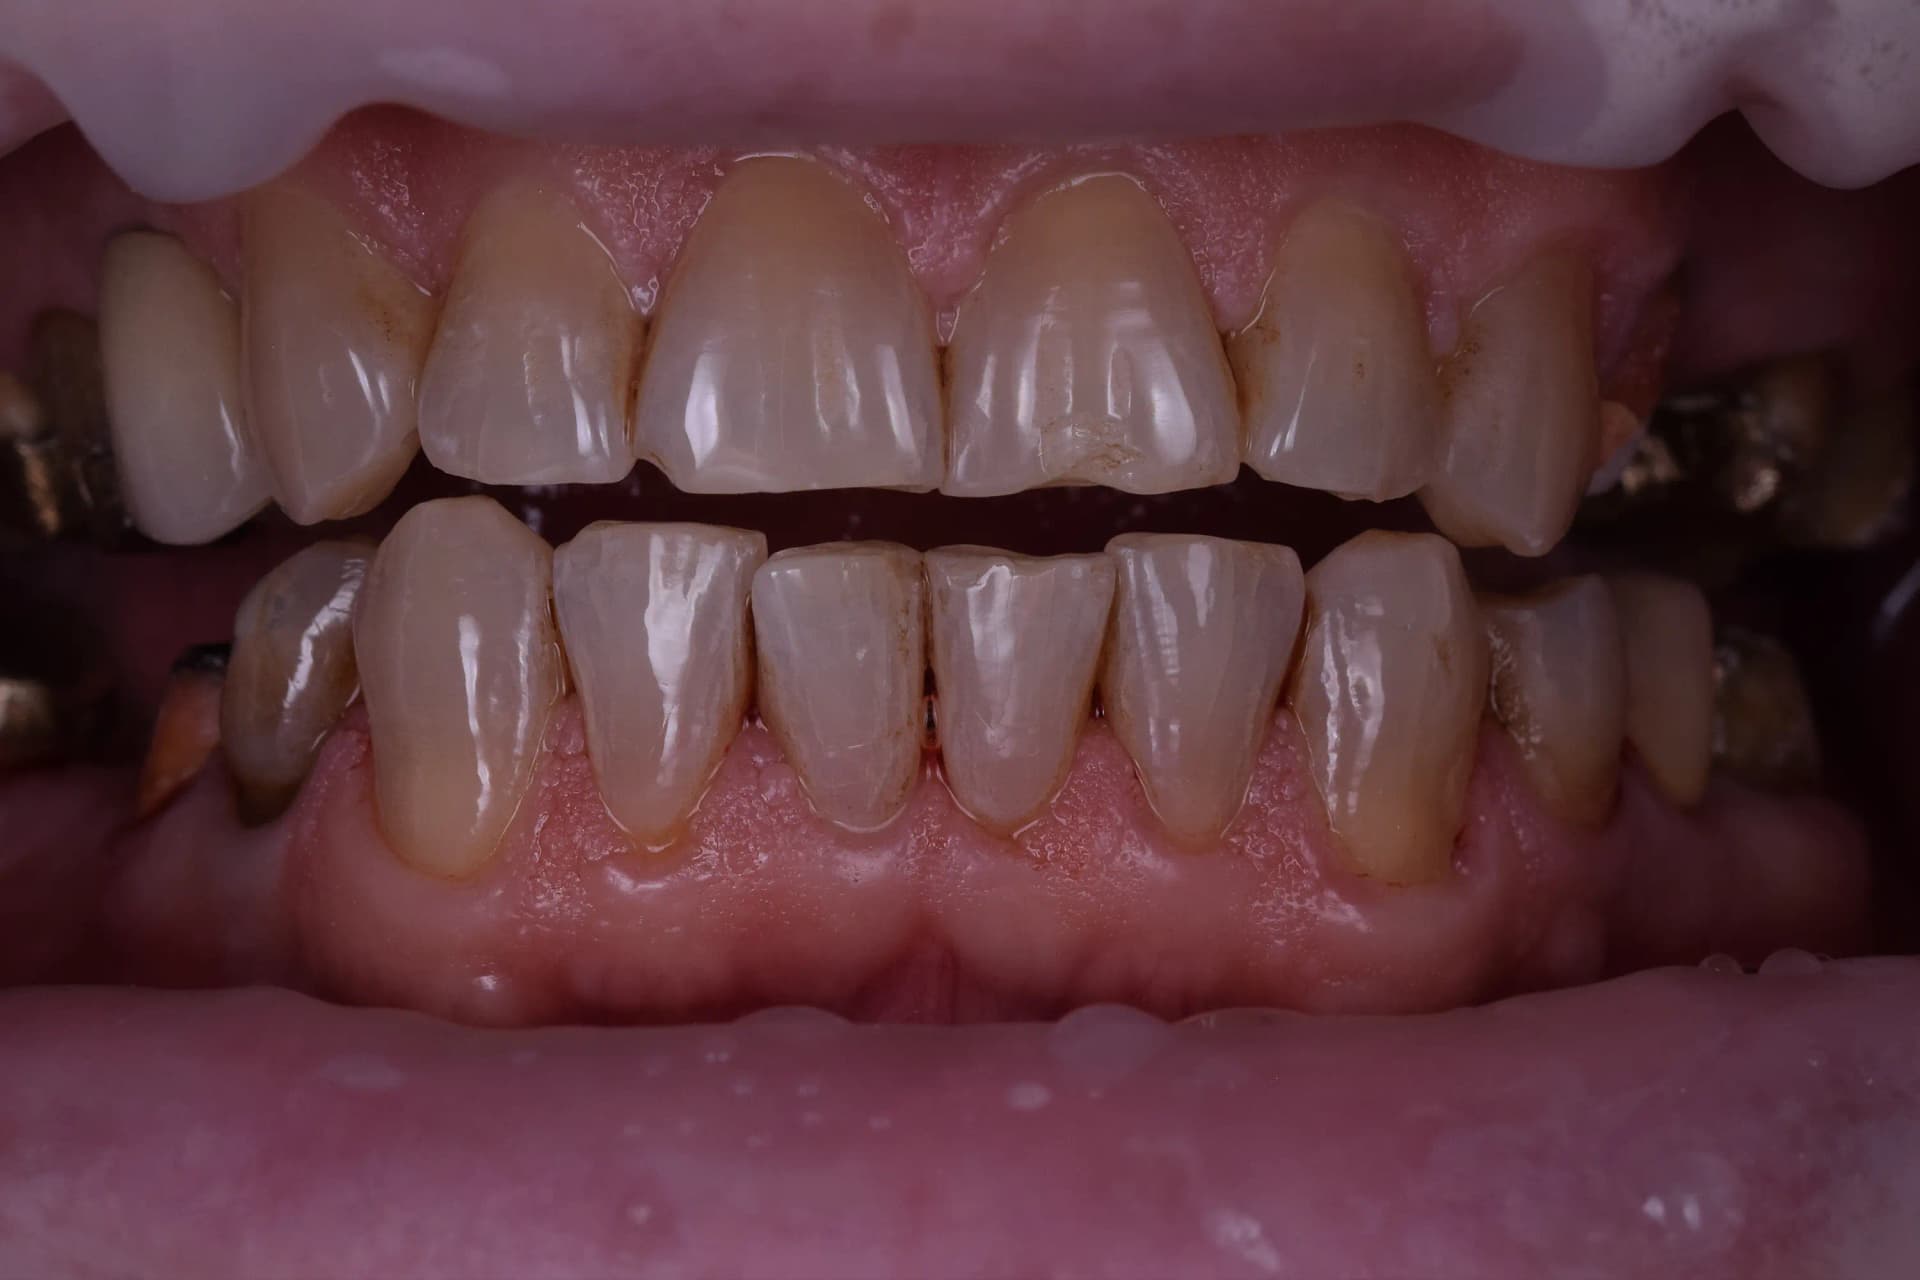

Pacientul s-a prezentat în clinica noastră nemulțumit de aspectul general „îmbătrânit” al zâmbetului. Fotografia inițială relevă o dantură afectată de trecerea timpului, cu o culoare neuniformă și semne vizibile de neglijență a igienei orale în trecut. Obiectivul a fost nu doar îmbunătățirea estetică, ci și restabilirea sănătății orale complete, pornind de la o bază solidă.

Principala dificultate a acestui caz a constat în gestionarea uzurii dentare accentuate (tocirea marginilor incizale), vizibilă în special la dinții frontali inferiori, combinată cu discromii (pete) profunde și prezența tartrului. De asemenea, existența unor lucrări protetice vechi (vizibile în zonele laterale) și a obturațiilor neadaptate a necesitat o abordare complexă, care să armonizeze dinții naturali cu noile restaurări.